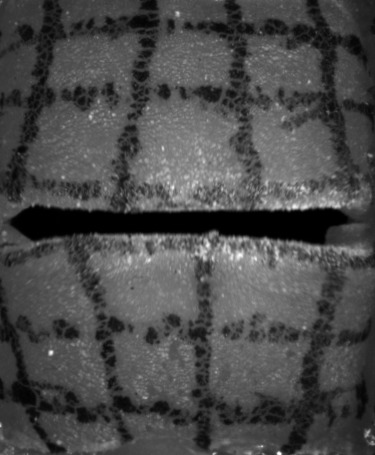

High-speed Camera

The high-speed camera provides a sequence of mono-chromatic images, as shown in Fig. 3. These images can be described as a function of intensities with an image resolution , the screen-space coordinates and with being the currently sampled frame of the video with many frames in total. Then, and denote the estimated motion of the screen-space coordinate at time along the longitudinal and lateral axis, respectively, resulting in the motion vector field:

We applied the sparse to dense optical flow algorithm based on the Lucas-Kanade feature tracker with pyramids by [25], which is available in OpenCV [26]. Such dense optical flow algorithm estimates a motion for every pixel of the input image, but tends to oversmooth flows (see Fig. 4(a)), which produces artifacts at edges. To mitigate this problem, we apply a mask (see Fig. 4(b)), which helps to distinguish the vocal folds from the gap between them. We use the intensity values for the mask segmentation with a subsequent median filter for more robustness to noise. Using the mask (see Fig. 4(c)), we set the motion vectors inside the gap explicitly to zero vectors, since there is no vocal fold movement. For consistency with the remaining data, the motion in the image plane is converted to physical domain units. The high-speed images and the resulting optical flows are discrete in space (individual pixels) and in time (individual frames). We interpolate the resulting discrete vector piecewise bilinearly in space with continuity and we interpolate quadratically with continuity in time to extract a continuous time-dependent two-dimensional vector field.